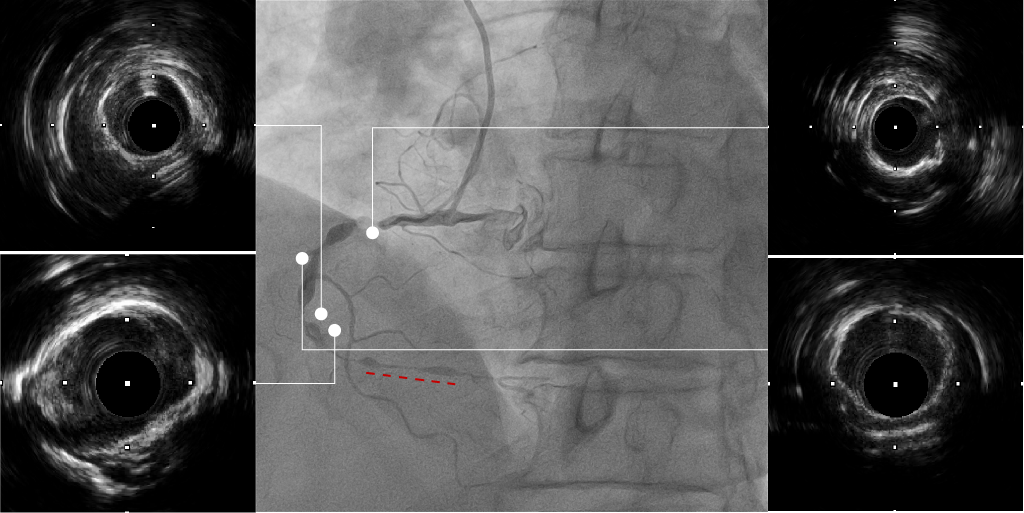

ROTA后评估

IVUS可见RCA近中段弥漫钙化病变,多>270°钙化环,3# 近端钙化壁较厚,可见旋磨后多重反射影;近中段病变扩张不充分,钙化环未见明显断裂,IVUS导管未能通过远端病变处。

IVUS无法通过远段

ROTA后评估远段

IVUS结果:远端钙化处可见360°钙化环断裂,多重反射影;远端血管直径约2.5mm。

再次IVUS评估

IVUS结果:可见近段及中段多处钙化环断裂,管腔狭窄明显改善;远端钙化环较厚未见明显断裂,管腔扩张不充分。

前后IVUS对比

最终CAG和IVUS

术后造影及IVUS可见支架膨胀及贴壁良好,支架远近端未见夹层血肿。